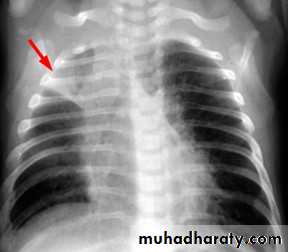

Right upper lobe collapse has distinctive features, and is usually easily identified on frontal chest radiographs .

Collapse of the right upper lobe is usually relatively easy to identify on frontal radiographs. Features consist of :

increased density in the upper medial aspect of the right hemithorax

elevation of the horizontal fissure

loss of the normal right medial cardiomediastinal contour

elevation of the right hilum

hyperinflation of the right middle and lower lobe result in increased translucency of the mid and lower parts of the right lung

right juxtaphrenic peak

A common cause of lobar collapse is a hilar mass. When a right hilar mass is combined with collapse of the right upper lobe, the result is an S shape to elevated horizontal fissure. This is known as Golden S sign .

Non-specific signs indicating right sided atelectasis are also usually present including:

elevation of the hemidiaphragm

crowding of the right sided ribs

shift of the mediastinum and trachea to the right